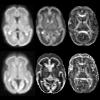

Diffusion Kurtosis Imaging of premature newborns

Diffusional kurtosis imaging (DKI) is a recently proposed extension of the conventional DTI model. It has been shown to offer more sensitive characterization of neural tissues than DTI. So far, DKI has only been applied to adult human and small animal studies, but not yet to human newborns. In this work, we present an optimized workflow for the acquisition and processing of DKI images of newborns. First, optimal set of diffusion weighting gradients for DKI studies of newborn subjects is proposed. Optimized gradients allow to estimate DKI parameters with the highest precision.